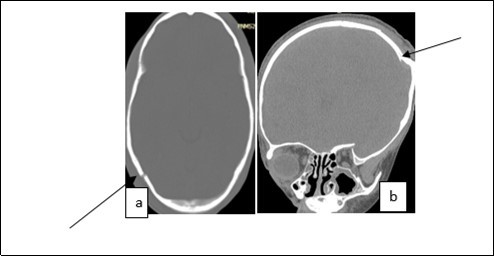

From the point of view of care, two (n=2) (10.52%) children received medical treatment compared to 17 (89.48%) children who received medical-surgical treatment. Neurosurgical treatment consisted of evacuation of the extra dural hematoma. This involved making a skin incision, trepanation (Figure 3 a), a preserved cranial bone flap, evacuation of the extra-dural haematoma (Figure 3 b), haemostasis either of the bone using bone wax or venous or arterial haemostasis by bipolar coagulation as appropriate, suspension of the dura mater (Figure 3 c), replacement of the bone flap (Figure 3 d) and finally suturing of the scalp in two planes. Figure 1, Figure 2, Figure 3.

Figure 2.Image of a brain CT scan without contrast agent injection in a bone window, axial section showing a right parieto-occipital fracture (a), coronal section showing a left parietal skull depressed fracture (b)